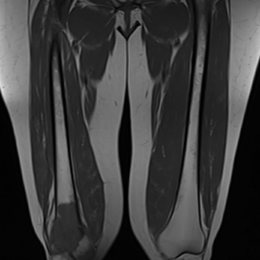

Radiographic imaging is used to help form a diagnosis. These include X-Ray, MRI, CT and Bone Scans.

An example of an UPS MRI is shown.